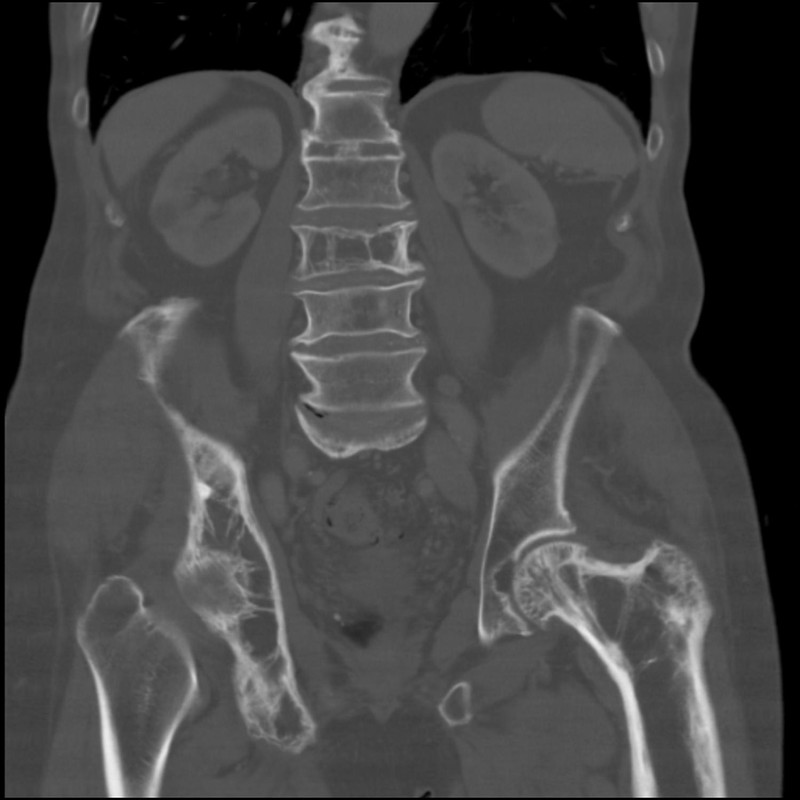

paget disease of bone

A 72-year-old man presents for a routine follow-up in his general practitioner's office regarding his type 2 diabetes and hypertension management. He reports feeling generally well, with no specific complaints of bone pain, fractures, or changes in his hat size. His past medical history includes well-controlled type 2 diabetes mellitus, essential hypertension, and obesity. He denies any recent falls or trauma.During the visit, his vital signs are stable: temperature 36.80C, blood pressure 130/80 mmHg, pulse 70/min, respirations 16/min, and oxygen saturation 98% on room air. Physical examination is unremarkable, with no bony tenderness or deformities noted. Routine laboratory tests ordered during his visit reveal several abnormal findings.Given the patient's presentation and laboratory findings, what is the most likely diagnosis and the initial management strategy?